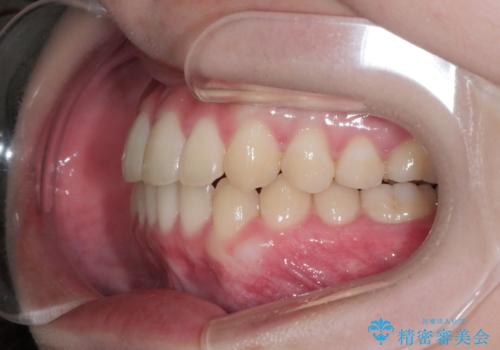

- 非抜歯、インビザライン治療希望の患者様です。

右の犬歯が八重歯になっており、通常であれば抜歯を選択する可能性が高くなりますが、

マイクロインプラントと呼ばれる骨に打ち込むネジを使用し、非抜歯での治療計画を立てました。

マイクロインプラントを使用することで非抜歯での治療が可能となりました。

マイクロインプラントを使用せずに無理に非抜歯治療を行った場合、

治療後に出っ歯になってしまうなどの問題が起きる可能性が高いです。